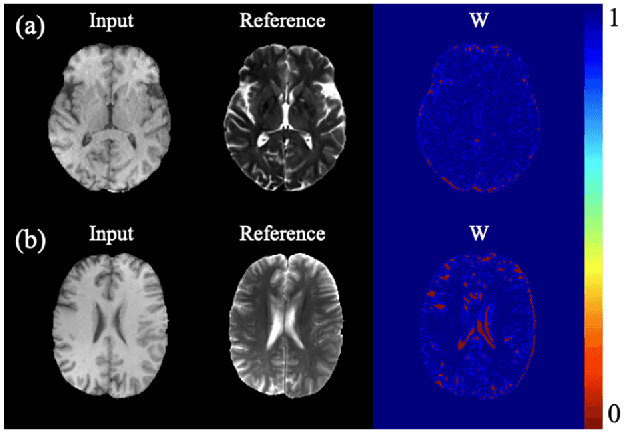

Abstract:The current mainstream multi-modal medical image-to-image translation methods face a contradiction. Supervised methods with outstanding performance rely on pixel-wise aligned training data to constrain the model optimization. However, obtaining pixel-wise aligned multi-modal medical image datasets is challenging. Unsupervised methods can be trained without paired data, but their reliability cannot be guaranteed. At present, there is no ideal multi-modal medical image-to-image translation method that can generate reliable translation results without the need for pixel-wise aligned data. This work aims to develop a novel medical image-to-image translation model that is independent of pixel-wise aligned data (MITIA), enabling reliable multi-modal medical image-to-image translation under the condition of misaligned training data. The proposed MITIA model utilizes a prior extraction network composed of a multi-modal medical image registration module and a multi-modal misalignment error detection module to extract pixel-level prior information from training data with misalignment errors to the largest extent. The extracted prior information is then used to construct a regularization term to constrain the optimization of the unsupervised cycle-consistent GAN model, restricting its solution space and thereby improving the performance and reliability of the generator. We trained the MITIA model using six datasets containing different misalignment errors and two well-aligned datasets. Subsequently, we compared the proposed method with six other state-of-the-art image-to-image translation methods. The results of both quantitative analysis and qualitative visual inspection indicate that MITIA achieves superior performance compared to the competing state-of-the-art methods, both on misaligned data and aligned data.